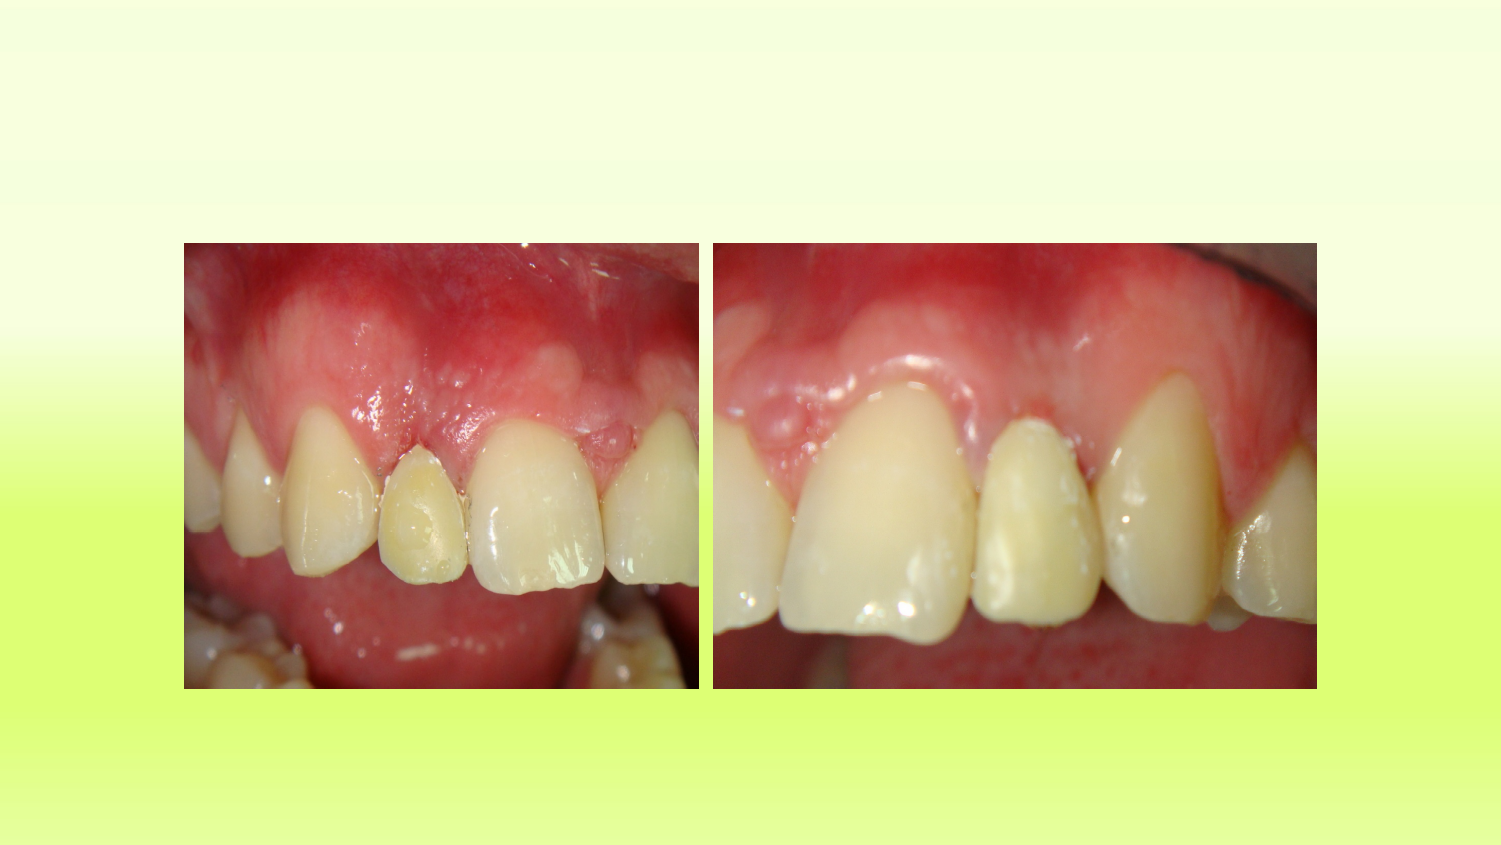

Case 12

“Vector” Implant placement in the area of 22 and 12 missing teeth is the only correct solution.